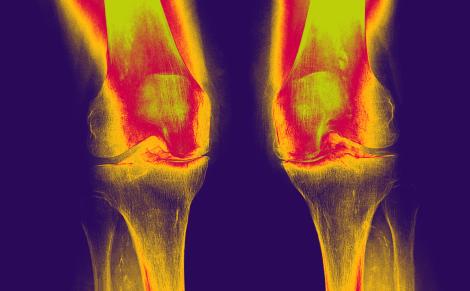

L’arthrose est la plus fréquente des maladies articulaires et constitue la première cause d'invalidité dans les pays industrialisés. En France, elle toucherait environ 10 millions de personnes, avec un coût estimé de plus de 3,5 milliards d'euros.

Il concerne toutes les gonarthroses de l’adulte, y compris l’arthrose traumatique du sujet jeune.